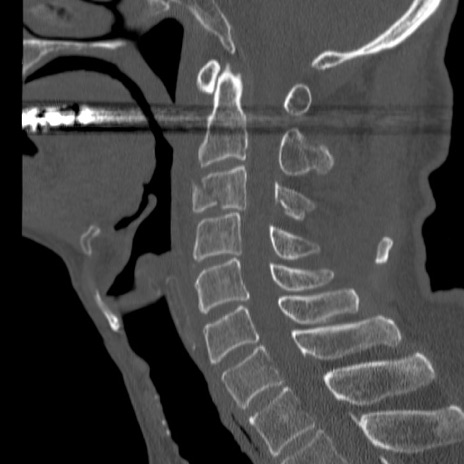

症例46 頚椎CT(矢状断像)

【症例】80歳代男性

【主訴】両側頚部〜上肢のしびれ

【現病歴】昨日、自宅内で転倒、その後より上記症状あり。意識障害なし。

【身体所見】両側上肢のallodynia(熱痛覚過敏)あり。MMTおよびDTRは正確な所見取れず。両上肢の挙上はなんとか可能。

異常所見と診断は?